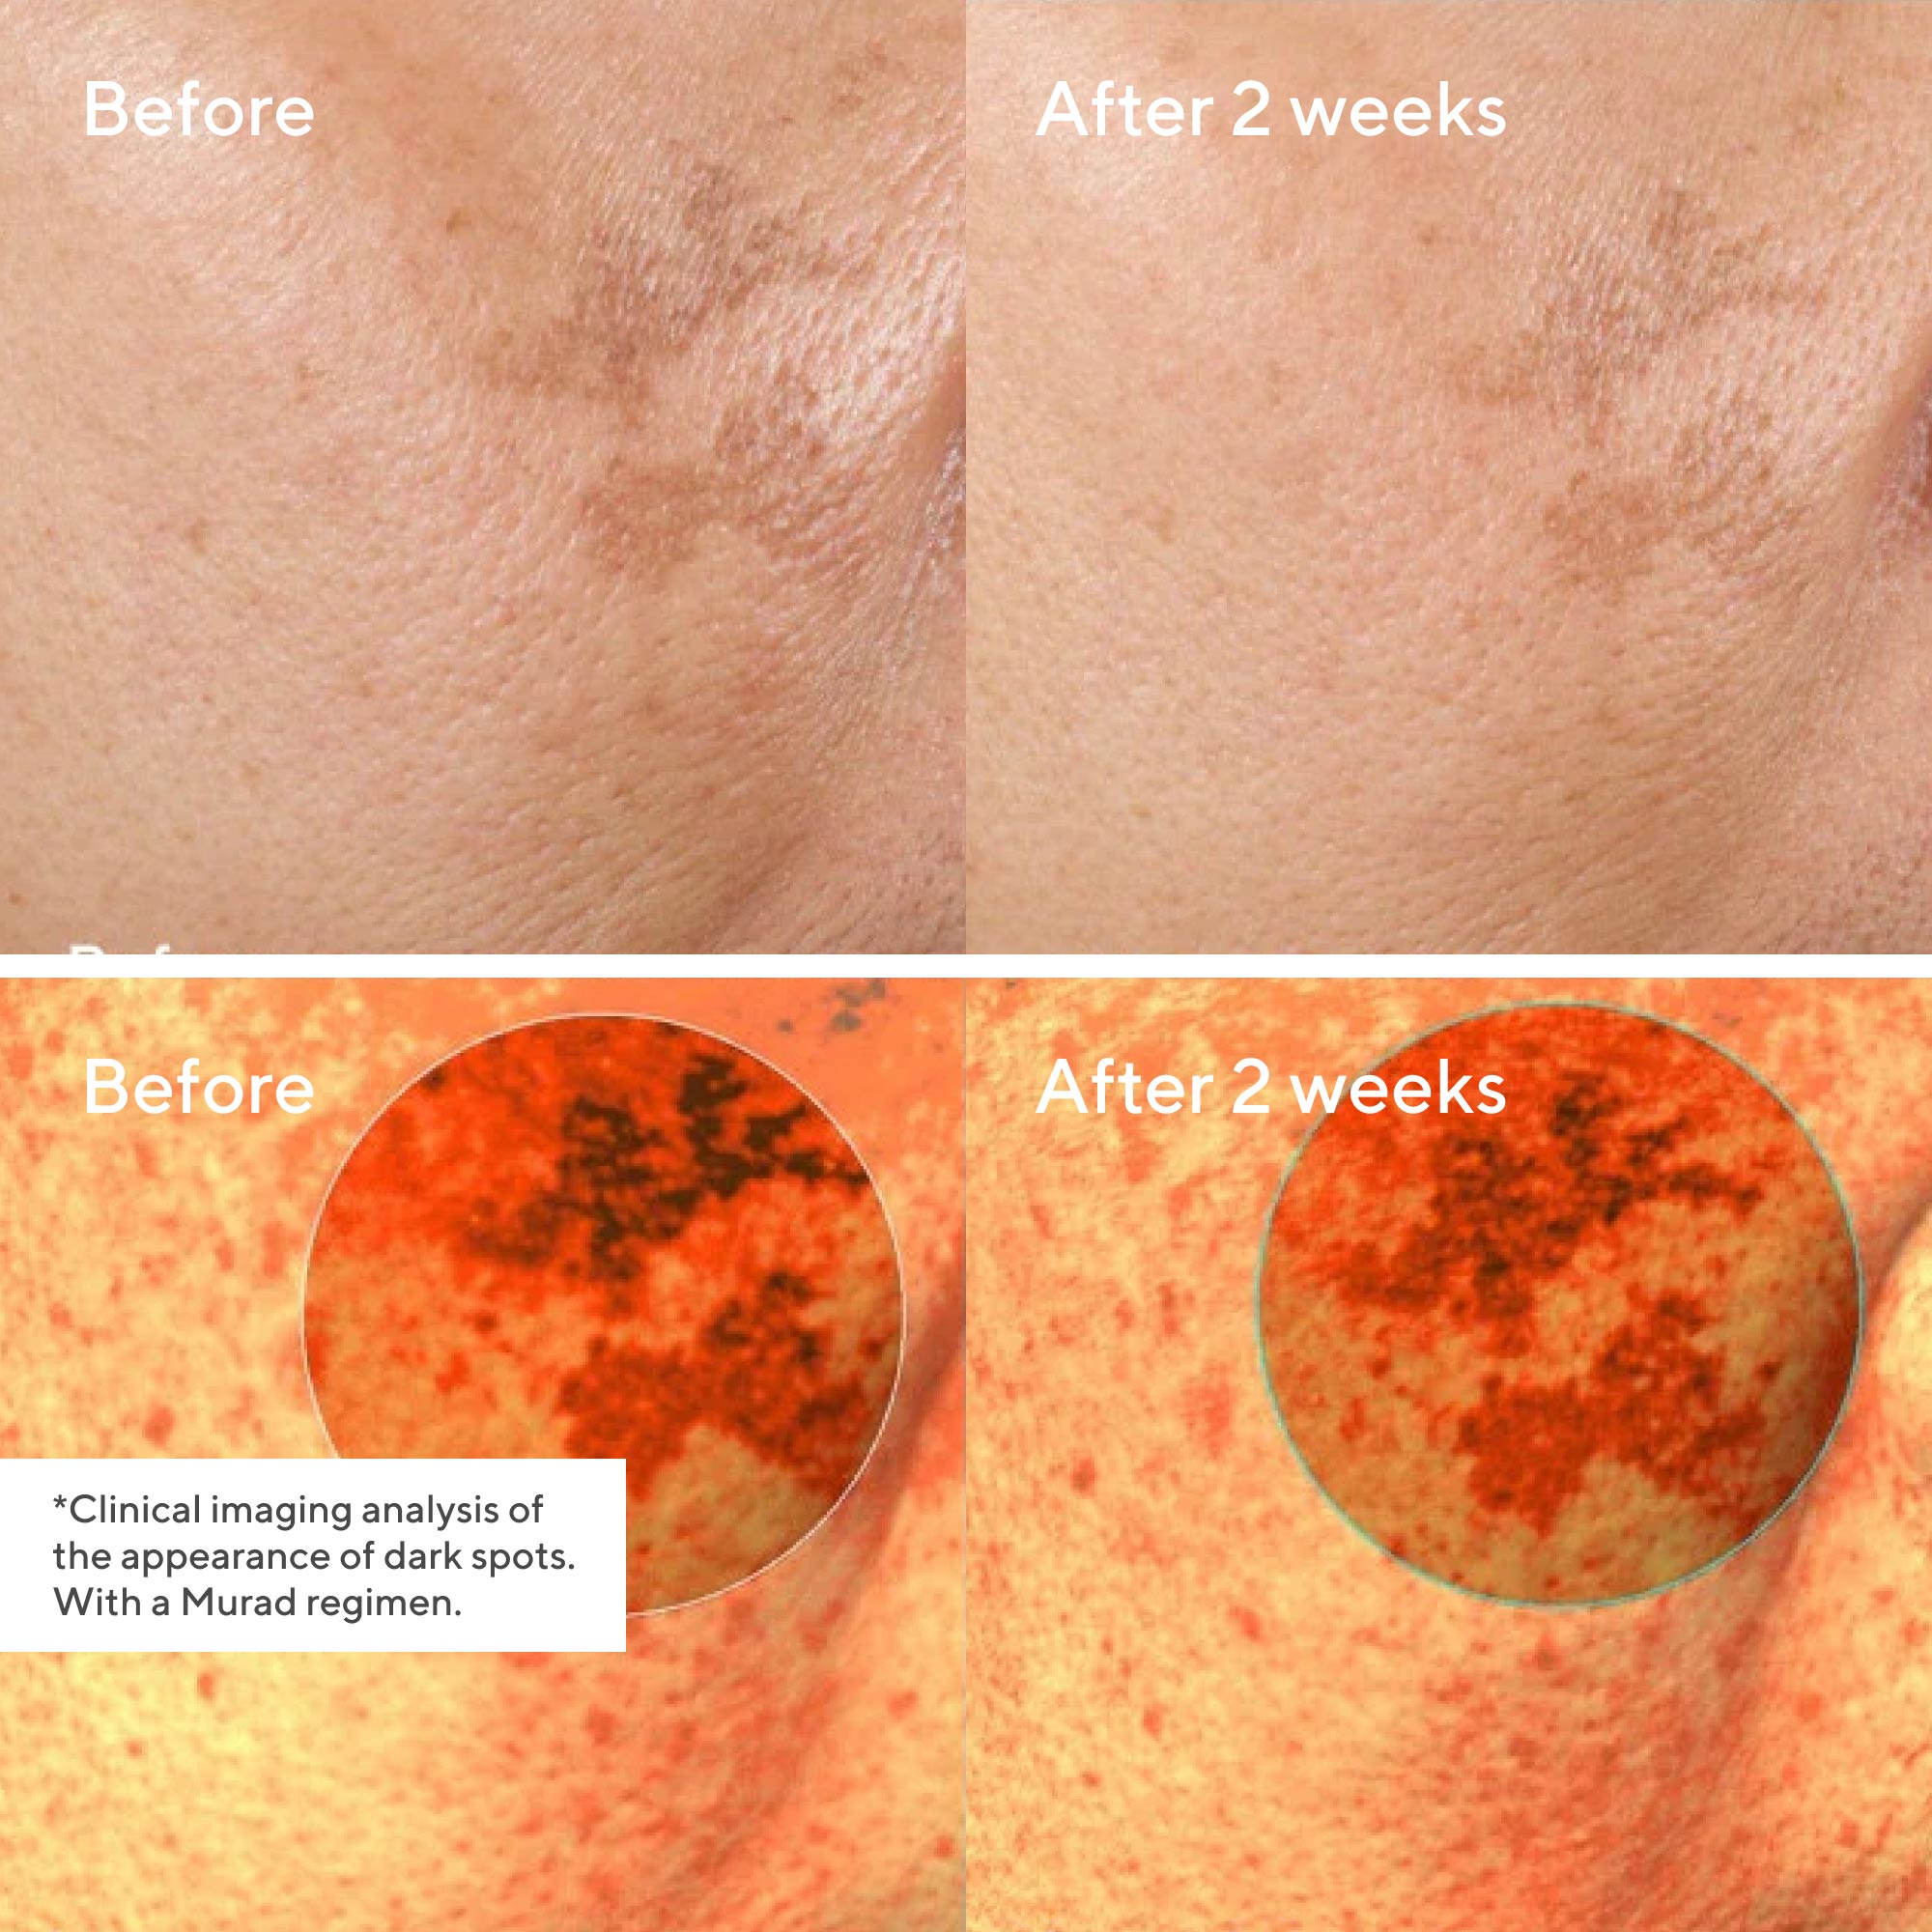

Die nächste Generation von Dr. Murads leistungsstarken aufhellenden Inhaltsstoffen bekämpft selbst die hartnäckigsten dunklen Flecken und behandelt Ihre Haut mit der gleichen Sorgfalt wie ein Dermatologe. Dieses transformative Serum für die tägliche Anwendung geht mit dem antioxidativen Resorcinol einen Schritt über die Korrektur hinaus und hilft, dem Auftreten dunkler Flecken vorzubeugen - für einen gleichmäßigeren Hautton in der Zukunft. Glykolsäure, eines der ersten und begehrtesten Peelings in Dr. Murads dermatologischer Praxis, entfernt stumpfe Oberflächenzellen, um die natürliche Ausstrahlung, das Eindringen und die Leistung der Inhaltsstoffe für bessere Ergebnisse zu verbessern. *Klinisch nachgewiesene Ergebnisse durch instrumentelle Messung von Bereichen mit dunklen Flecken. Mit Murad-Kur. †Mit Murad-Kur.

Reduzieren Sie schnell das Aussehen dunkler Flecken in 14 Tagen - ohne Arztbesuch! Dieses Serum - mit wirksamen Inhaltsstoffen wie der patentierten Resorcinol-Technologie und Glykolsäure - geht einen Schritt weiter als die Korrektur, um das Auftreten von dunklen Flecken zu verhindern und einen gleichmäßigeren Hautton zu erzielen.

Unretuschierte echte Ergebnisse

Die TestteilnehmerInnen stimmen in nur 14 Tagen zu:

84% zeigten eine Verringerung des Aussehens von Hyperpigmentierung*